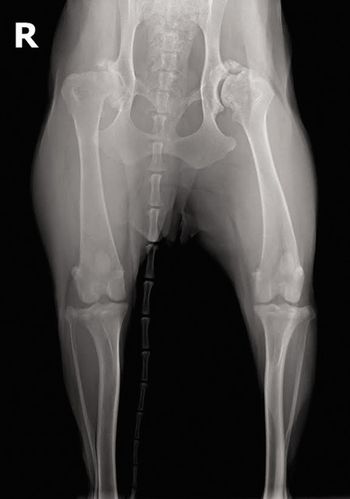

Are you an X-ray expert? Test your skills with this case of an unsteady standard poodle pup.